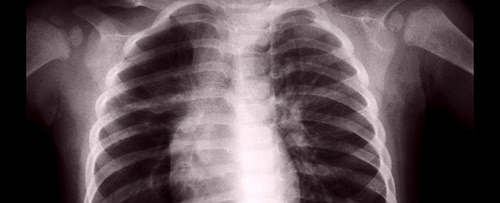

这里是它看起来的样子: